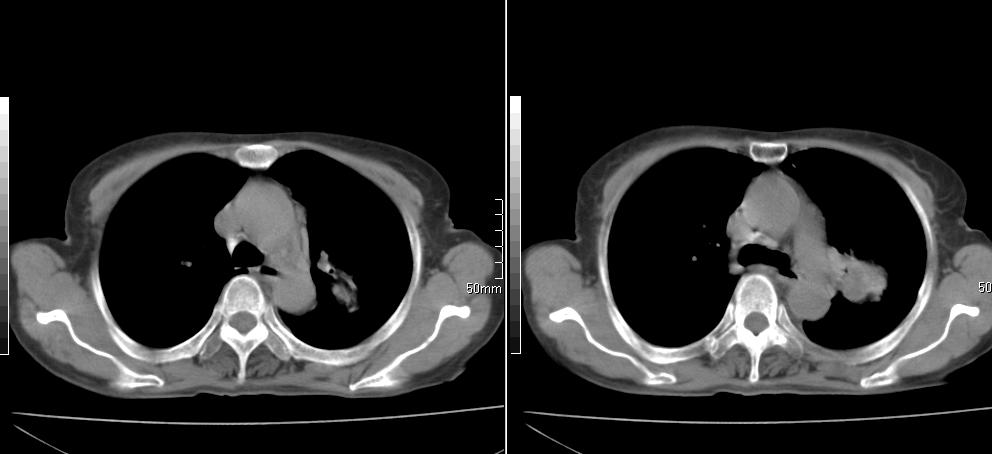

标题: CT26857:女,60岁,胃部不适前来就诊,不咳嗽,乏力,胸椎 [打印本页]

标题: CT26857:女,60岁,胃部不适前来就诊,不咳嗽,乏力,胸椎

1、胸椎有骨质破坏伴周软组织,考虑胸椎转移。2、考虑左肺上叶尖后段支气管开口区周围型肺癌可能。

1、胸椎有骨质破坏伴周软组织,考虑胸椎转移。2、考虑左肺上叶尖后段支气管开口区周围型肺癌可能。建议行纤支镜检查!

1、胸椎有骨质破坏伴周软组织,考虑胸椎转移。2、考虑左肺中央型肺癌可能。

支持中央型肺癌,胸椎转移。

1)考虑左肺中央型肺癌。2)胸椎转移瘤不排除;建议行mri检查。